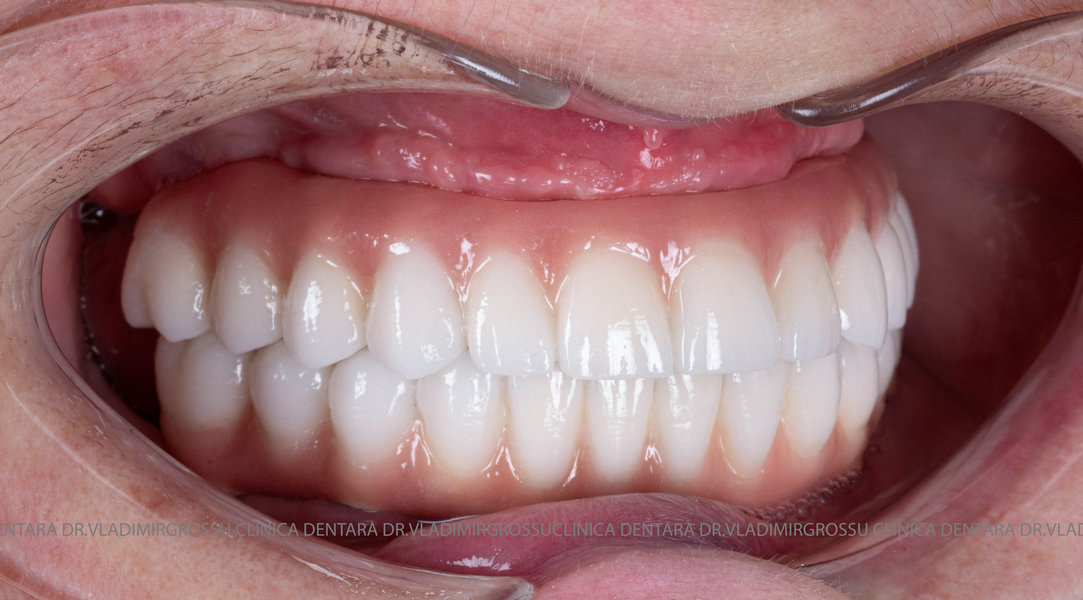

- A doua etapă are loc la aproximativ 6 luni după intervenție, când se realizează proteza definitivă, care este fixată pe implanturi prin intermediul unor piese numite multiunit-uri. Această etapă presupune lucrul la nivelul multiunit-urilor, nu direct pe implanturi, reducând astfel riscul de complicații.

Caz 1

- Posibilitatea realizării unei proteze cu 12-14 dinți, oferind un aspect estetic natural și funcționalitate optimă.